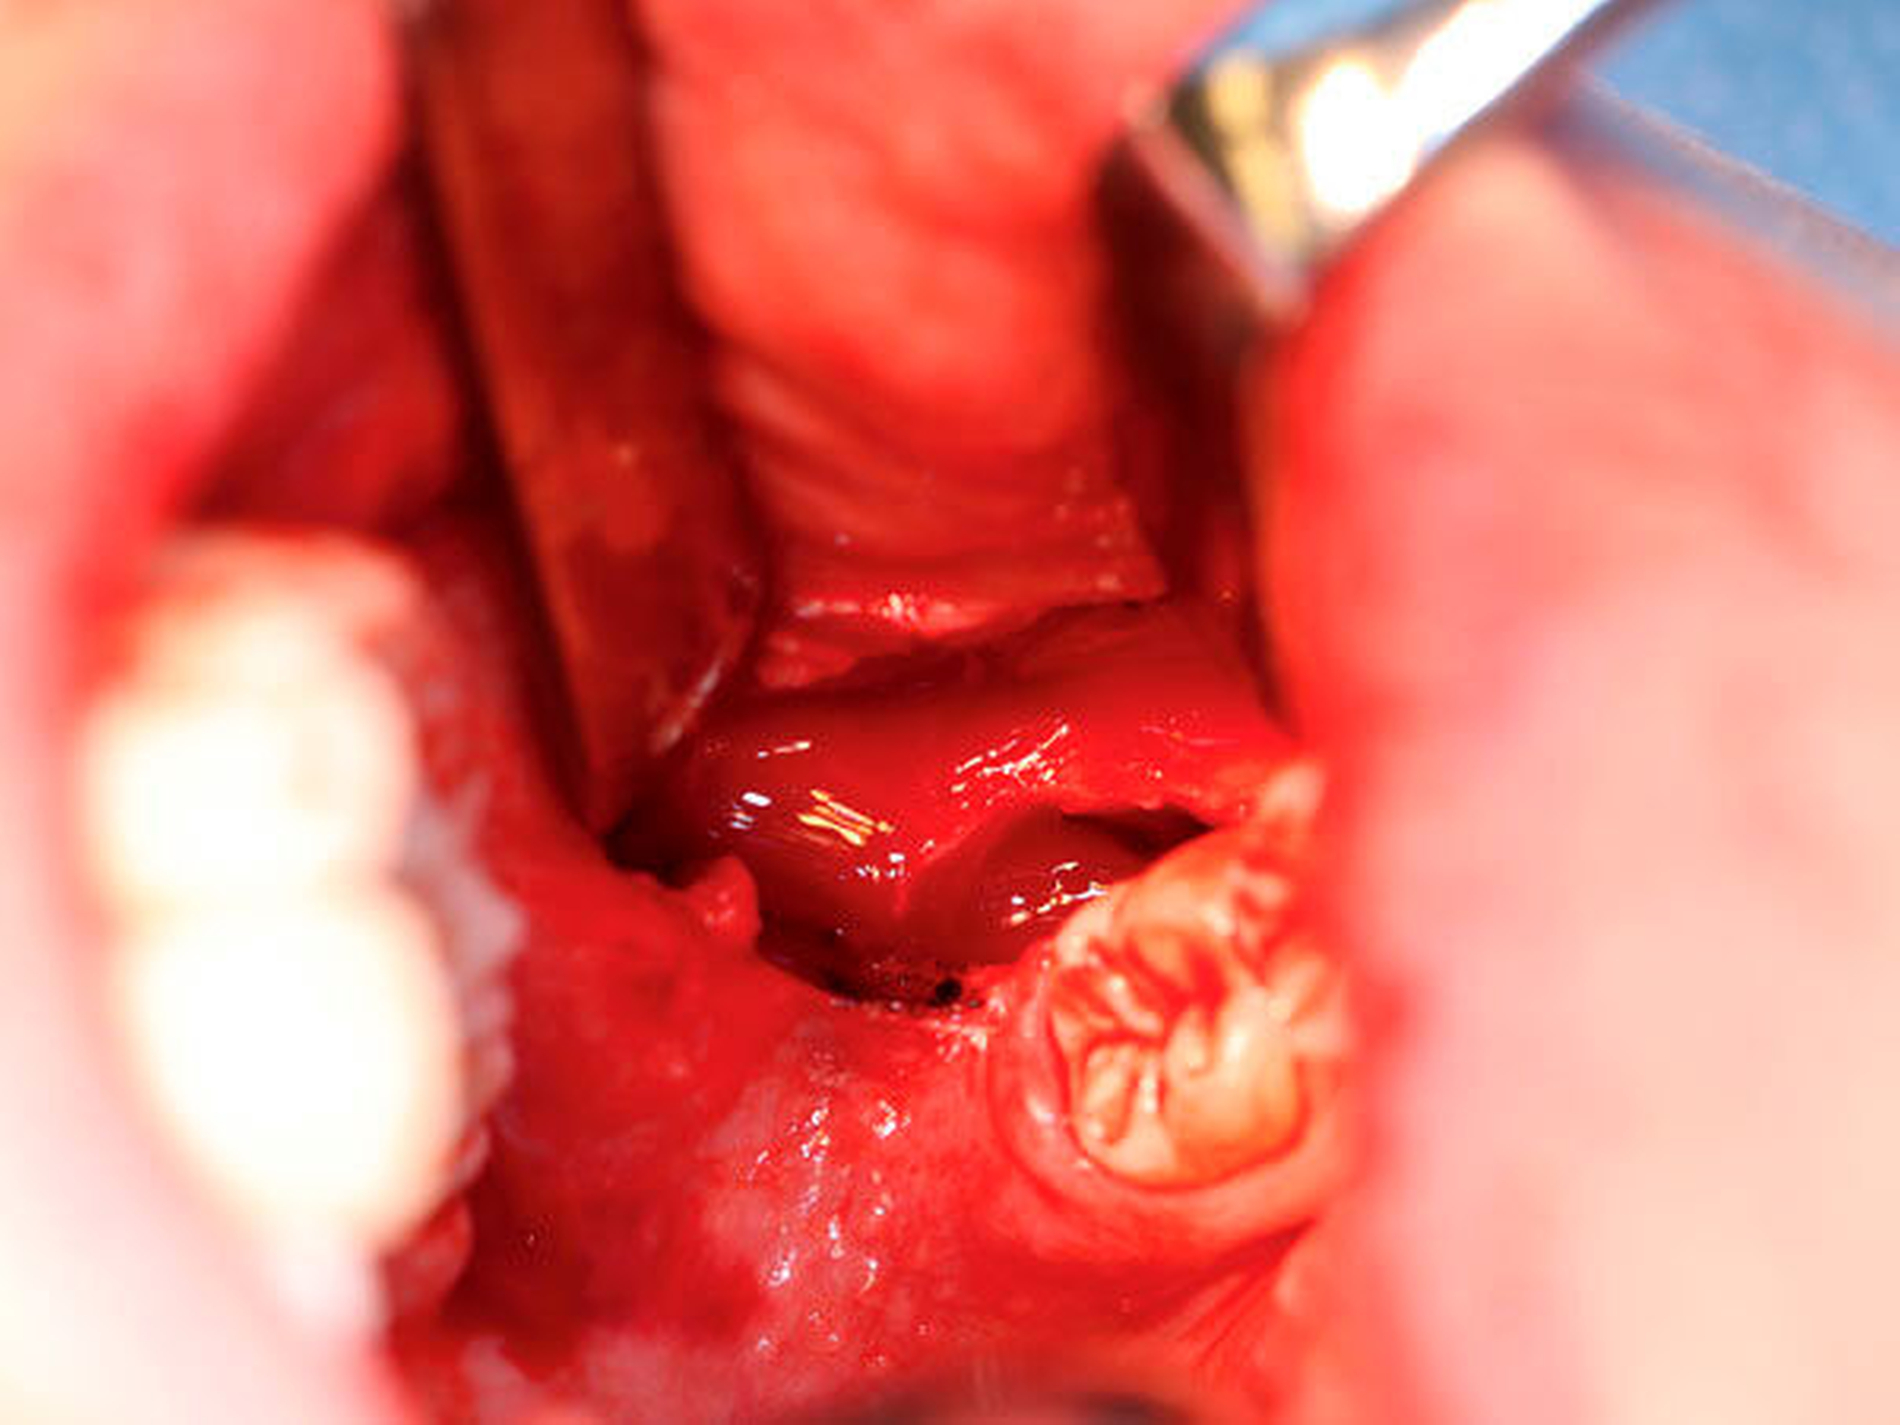

Es erfolgte die notfallmäßige Bergung des Zahns in Intubationsnarkose. Hierbei wurde über den bereits angelegten Zugang im Unterkiefer entlang des aufsteigenden Unterkieferastes (Abbildung 4) das lingual gelegene Weichgewebe exploriert. Die leere Alveole 38 wurde gespült und auf weitere Zahnfragmente inspiziert. Der dislozierte Zahn ließ sich schließlich direkt unterhalb des in den Unterkiefer eintretenden N. alveolaris inferior und mit enger Lagebeziehung zum N. lingualis darstellen (Abbildung 5) und konnte komplikationslos geborgen werden (Abbildung 6). Postoperativ zeigte sich sofort eine vollständig hergestellte Sensibilität der Unterlippe, des Kinns und der Zunge.